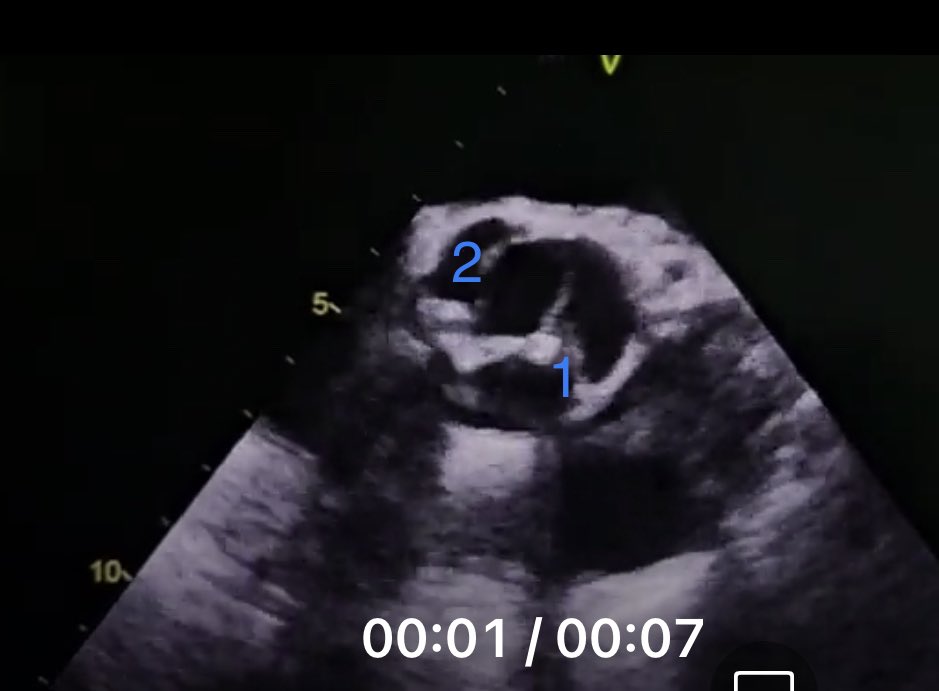

66 y/o male with ESLD admitted for hypoxia. Undergoing OLT evaluation

@ASE360 @GarySHuang @iamritu

What is the diagnosis?

1. PFO

2. ASD

3. Pulmonary AVM

4. Anomalous pulmonary vein